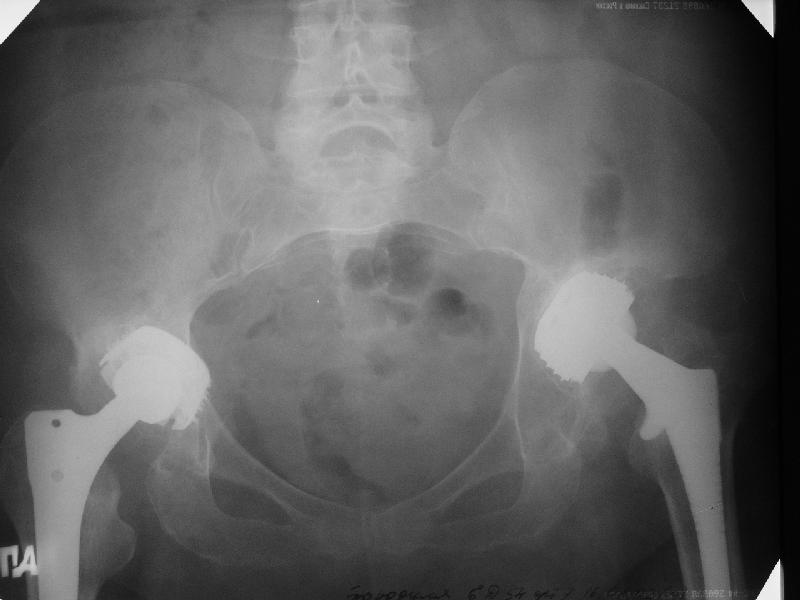

Август 2002 г.

24 апреля 2005 г. правый сустав фас (тут и болит)

24 апреля 2005 г. левый сустав фас